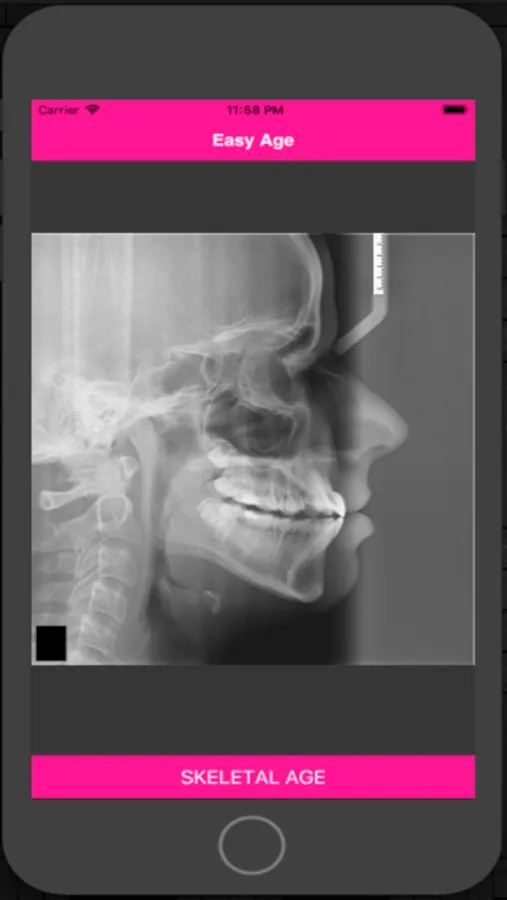

Easy Age is an app for the estimation of bone age through the cervical vertebrae maturation methods.

The changes that occur in the morphology of the cervical vertebrae C2, C3 and C4, present in routine lateral cephalograms can be used in the evaluation of bone maturation, in a reliable way and with the same clinical value of the assessment of the hand and wrist region.

Easy Age calculates bone age by methods:

- Hassel & Farman (1995)

- Mito et al (2002)

- Baccetti et al (2005)

Used in dentistry in orthodontics, jaw functional orthopedics, pediatric dentistry and implantology.